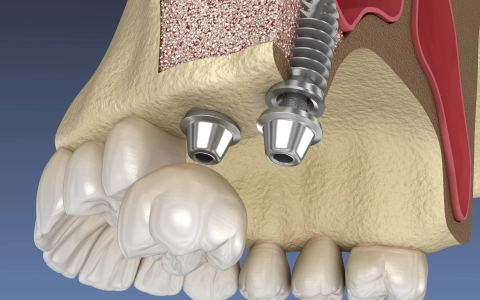

Sinus Lifting Tedavisi

Sinus lifting risksiz bir işlem değildir ama doğru hekim, doğru planlama ve uyumlu hasta üçlüsü ile yüksek başarı oranına sahiptir.